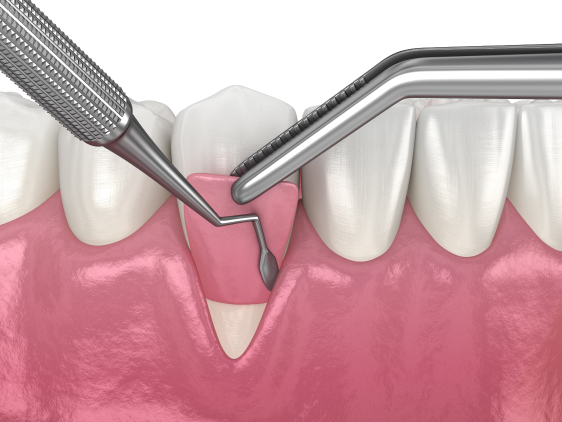

Complete oral rehabilitation may require regenerative procedures to get you the function and aesthetics you are looking for. These procedures can fall under the sub categories of Hard or Soft tissue regeneration or a combination of both. Our doctors are well versed in various different procedures and can provide you with an accurate assessment at a consult and after assessing your 3D reconstructed CT scan, intra oral pictures and clinical examination of your oral cavity.

At Apple Dental Implant Centres, you can be assured to find the right treatment suited to your case. Our doctors are well versed in all aspects of regenerative procedures, some of which are listed below.

Hard tissue Regeneration:

- Socket grafting

- Alveolar Ridge augmentation

- Direct or Indirect Maxillary Sinus Lift

- Ridge Split Bone augmentation

- Multiple other types of bone graft procedures decided on a case by case basis